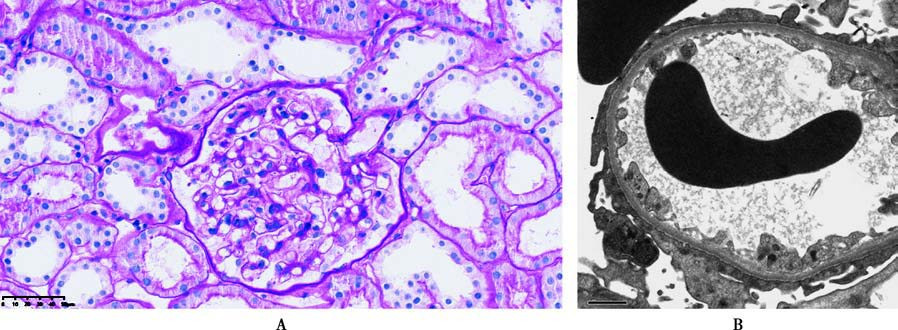

Figure 2 Pathological images of minimal change disease

A. Normal glomerulus in light microscopy (PAS staining);

B. Glomerulus in electron microscopy (extensive fusion of visceral epithelial cell foot processes).

In light microscopy, glomeruli show no significant abnormalities, though lipid degeneration may be observed in the proximal tubular epithelial cells. Immunopathological examination is negative. The characteristic finding in electron microscopy is widespread podocyte foot process effacement.